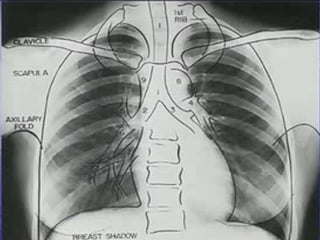

A densidade do pulmão,  não é distribuída uniformemente. 1 g/mL, próximo ao hilo  0,1 g / mL perifericamente. Mais de 50% de todos os alvéolos do pulmão estão localizados na periferia. Aplicação: a porção periférica do pulmão aparece relativamente vazia na radiografia de tórax.

A Variabilidade da densidade, também existe a partir de cima para baixo. os vasos sanguíneos estão mais dilatados nos campos pulmonares inferiores.  O aumento da distensão dos vasos do ápice para a base também ilustra o aumento das pressões de distensão vascular a uma taxa de 1 cmH2O para cada cm para baixo no pulmão.

A densidade dopulmão, não é distribuída uniformemente. 1 g/mL, próximo ao hilo 0,1 g / mL perifericamente. Mais de 50% de todos os alvéolos do pulmão estão localizados na periferia. Aplicação: a porção periférica do pulmão aparece relativamente vazia na radiografia de tórax.

A Variabilidade dadensidade, também existe a partir de cima para baixo. os vasos sanguíneos estão mais dilatados nos campos pulmonares inferiores. O aumento da distensão dos vasos do ápice para a base também ilustra o aumento das pressões de distensão vascular a uma taxa de 1 cmH2O para cada cm para baixo no pulmão.